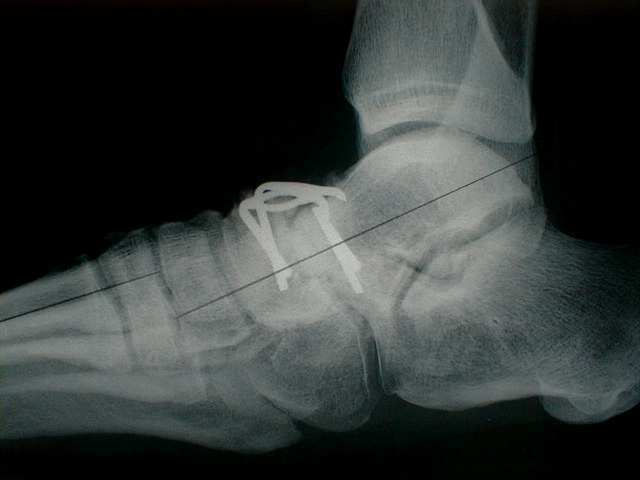

Arthrodèse talo-naviculaire

L'interventions se déroule sous anesthésie générale ou rachianesthésie. Une incision antérieure sur le coup-de-pied est pratiquée. L'articulation est abordée et le cartilage du talus et du naviculaire est retiré. Ces deux os sont fixés l'un à l'autre par une plaque ou des agrafes métalliques.

Il est à notre que ces 2 interventions peuvent être couplées.